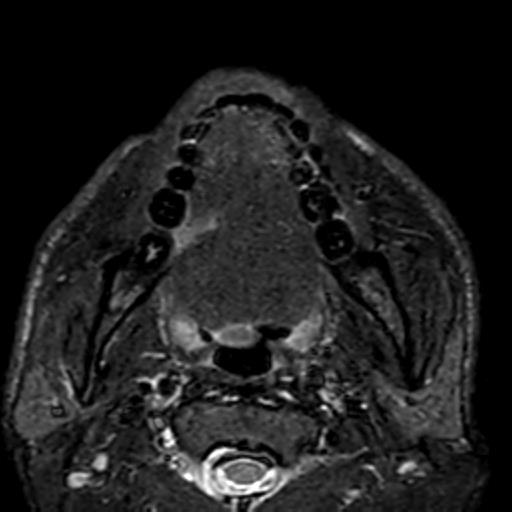

Fig. 2: Contrast-enhanced MRI T1 Fat sat reveals an enhancing irregular ulcer in right lateral border of tongue. No e/o cervical luymphadenopathy